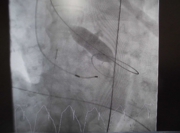

1、 冠状動脈造影

BAV治療前には、冠動脈造影を行い狭窄の有無を確認します。有意狭窄があれば、治療デバイスの準備を行います。